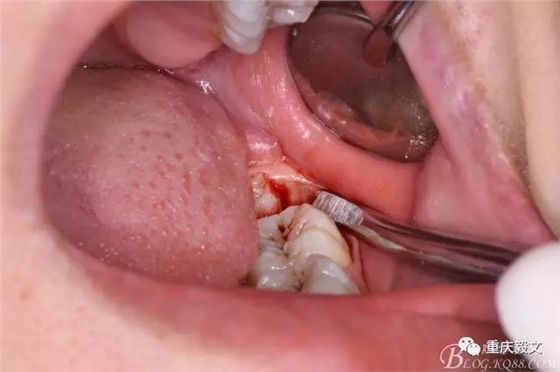

圖5.分離舌側(cè)牙齦

圖6.分離頰側(cè)牙齦,目的使牙冠和牙根能順利從牙齦軟組織脫位。